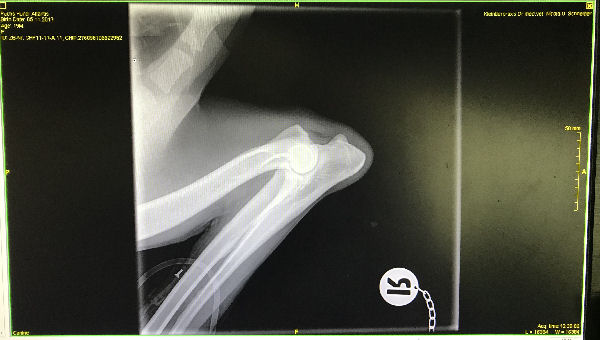

Atlantis - ED-Röntgen

img_5245-Atlantis-ocd